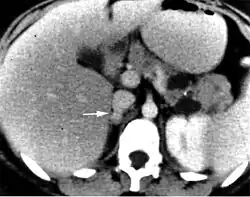

Tomografia komputerowa (TK) jest badaniem ogólnie dostępnym, charakteryzującym się dużą czułością (95–98%[16]). Guzy chromochłonne w obrazie TK charakteryzują się zwykle jednorodną strukturą i owalnym kształtem. Niekiedy można uwidocznić zmiany torbielowate, ogniska martwicy, wylewy, zwapnienia w świetle guza. Przy złośliwych postaciach pheochromocytoma istotna jest również możliwość zlokalizowania potencjalnych przerzutów.

Przy trudnościach diagnostycznych, zwłaszcza w przypadku guzów zlokalizowanych pozanadnerczowo, stosuje się rezonans magnetyczny. Uważa się, że właśnie w przypadku takiej lokalizacji rezonans wykazuje większą czułość. Przydatny jest również w różnicowaniu innych zmian w nadnerczach. Minusem metody jest mniejsza dostępność i swoistość oraz wyższy koszt.